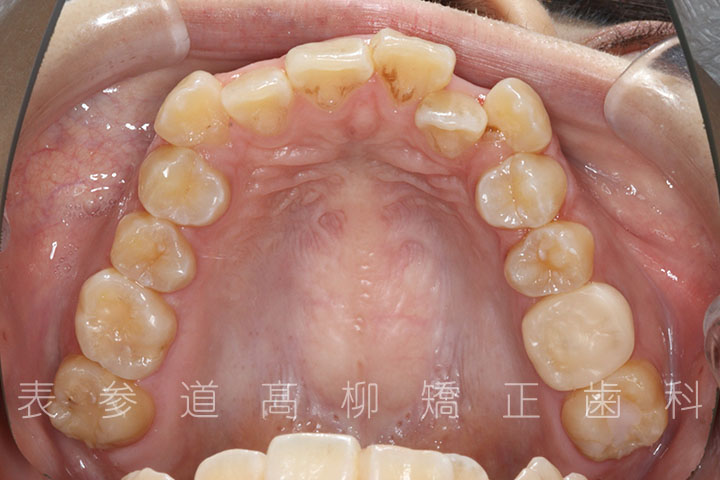

前歯のガタガタ感と開咬でお悩みの患者様の症例をご紹介いたします。

・上下前歯部叢生(凸凹歯並び)

術前術後の比較